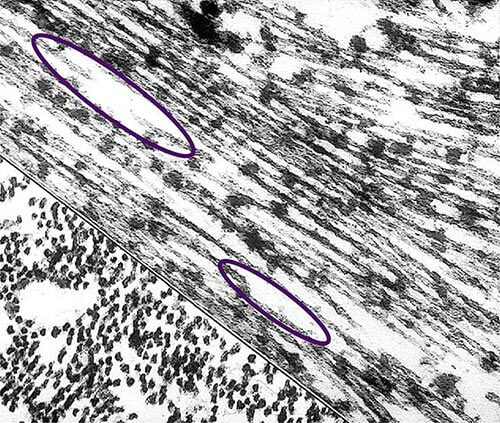

Under the Microscope

Scientists can also see the terrible effects of Alzheimer's disease when they look at brain tissue under the microscope. Scientists are not absolutely sure what causes cell death and tissue loss in the Alzheimer's brain, but the plaques and tangles in the figures below are prime suspects.

Alzheimer's tissue has many fewer nerve cells and synapses than a healthy brain.

Plaques, abnormal clusters of protein fragments, build up between nerve cells.

Dead and dying nerve cells contain tangles, which are made up of twisted strands of another protein.

More About Tangles

Tangles destroy a vital cell transport system made of proteins. This electron microscope picture shows a cell with some healthy areas and other areas where tangles are forming.

In healthy areas:

In areas where tangles are forming:

Nutrients and other essential supplies can no longer move through the cells, which eventually die.